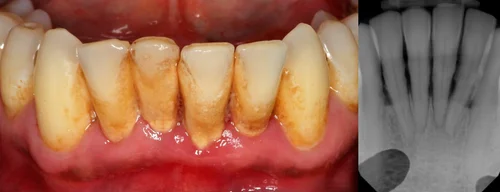

Not all cleanings are the same. Common check-up and cleaning costs vary. It is a deeper cleaning that goes under your gums to prevent or cure gum disease.

Scaling And Root Planing Best Dental In Houston Tx

Periodontal Deep Cleaning Houston Tx Garden Oaks Dental